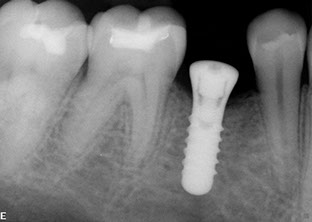

Dental implants have been used for decades to provide a stable support for missing teeth. Implants can be used to stabilize dentures, act as anchors for a bridge, or replace single teeth that are missing.

Implants are designed to be incorporated into the structure of the jawbone. A crown is then attached to the implant to function as a normal tooth. In most cases, implants take several months from placement to the final restoration(s). There is a period of healing while the implant becomes part of the body and stabilizes.